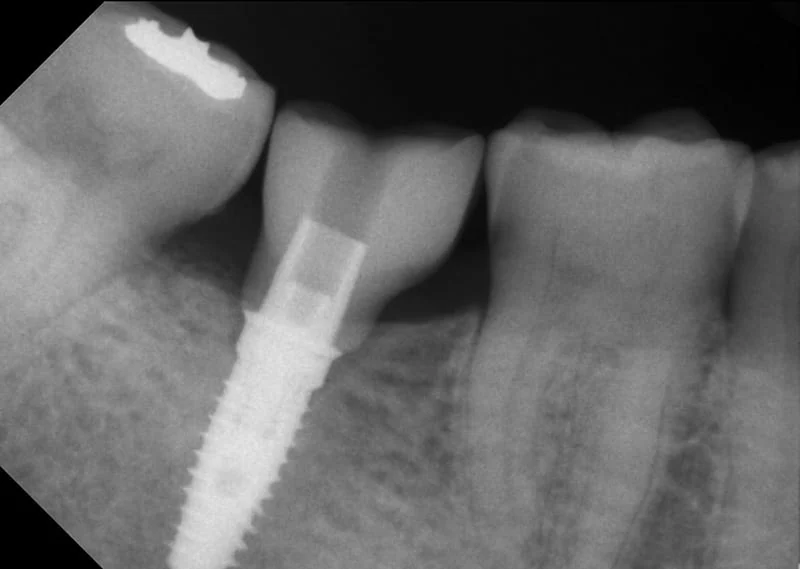

第二階段完成X光片 <圖五>

植牙假牙裝置完成X光片 <圖七>